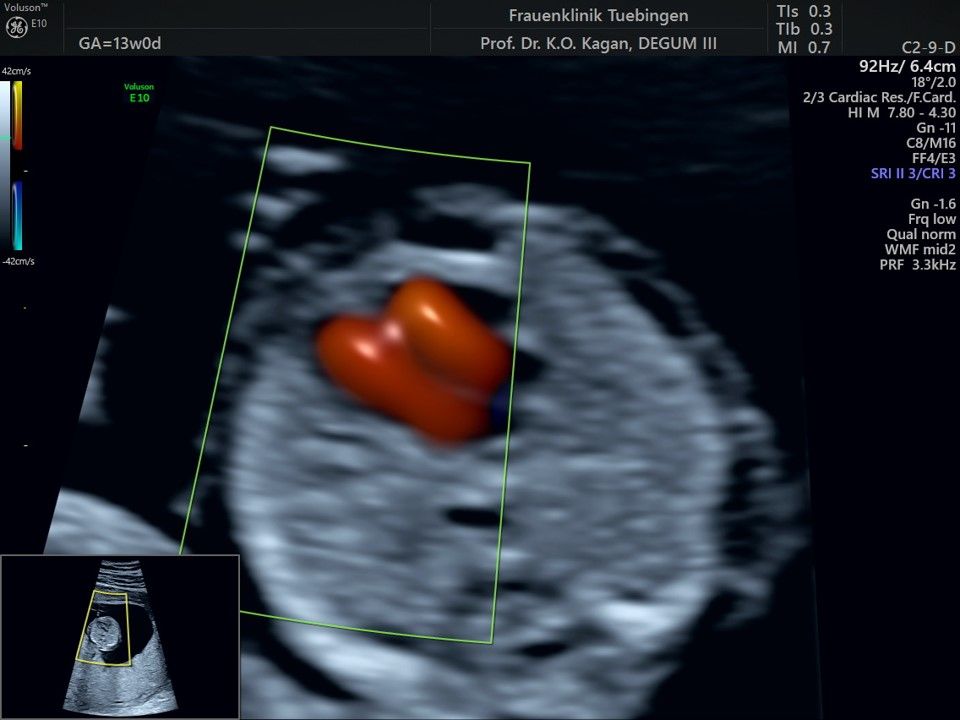

Das Ergebnis der Ultraschalluntersuchung ist wegweisend. Dabei wird der Fet vermessen, die Organe werden untersucht und die sonographischen Marker zur Risikoberechnung für Chromosomenstörungen werden beurteilt. Das sind: die Nackentransparenzdicke, Nasenbein sowie der Blutfluss in der rechten Herzhälfte und im Ductus venosus, einem Gefäß in der Leber des Feten.